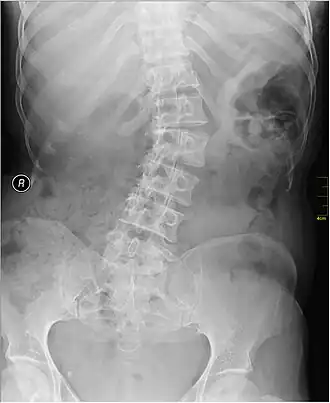

| Radiografia em que se observa deformação lateral da coluna causada por escoliose | |